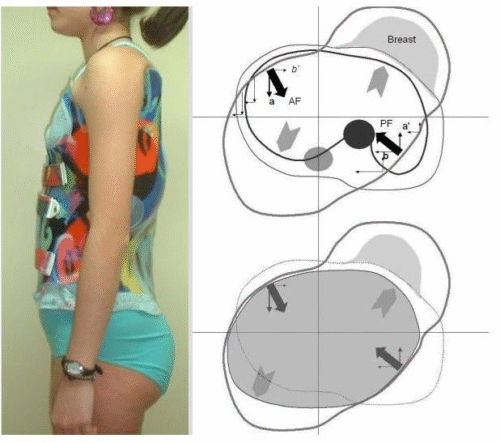

يتم تصميم الحزام بشكل مخصص لكل مريض بناءً على زاوية الاعوجاج (زاوية كوب)، ومكان الانحناء، وسن المريض، ومستوى نمو العظام.

التطور الكبير في تصميم الأحزمة الطبية جعل علاج اعوجاج العمود الفقري عند المراهقين أكثر نجاحًا وأقل إزعاجًا. باستخدام تقنيات التصوير الثلاثي الأبعاد والمحاكاة الرقمية، أصبح الحزام أكثر خفة وراحة، ويعطي نتائج أفضل في تصحيح الانحناء والتواء العمود الفقري.

الرسالة للأهل: إذا كان طفلك بحاجة إلى حزام طبي، اسأل الطبيب دائمًا عن التصميم الحديث المصنوع بتقنية ثلاثية الأبعاد، لأنه قد يكون الفرق بين علاج ناجح وفعّال، وبين نتائج محدودة.